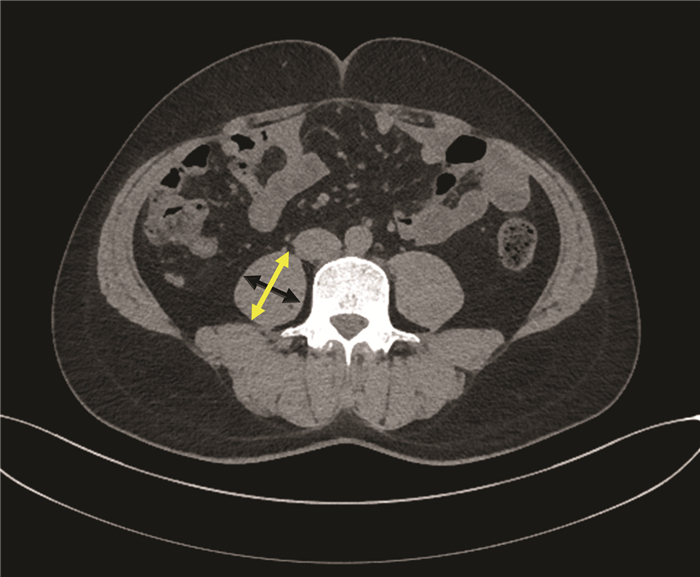

肝硬化失代偿期合并恶性胸膜间皮瘤并腹膜转移1例报告

卢利霞, 谢小青, 郑英, 刘鑫, 王建平, 王俊科, 王盼, 于晓辉

2022, 38(2): 418-419. DOI: 10.3969/j.issn.1001-5256.2022.02.030

摘要(916) HTML (261) PDF (2461KB)(60)

摘要: